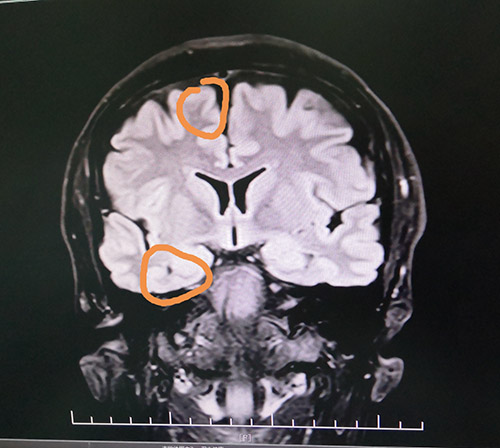

▲患者癲癇病灶區(qū)

藍(lán)十字腦科功能神經(jīng)外科主任楊忠旭博士認(rèn)真查看了劉先生各項檢查報告并聽取相關(guān)病情匯報,認(rèn)為患者腦組織結(jié)構(gòu)發(fā)生病變,引起癲癇發(fā)作,經(jīng)系統(tǒng)藥物治療無任何改善,應(yīng)用現(xiàn)代神經(jīng)影像學(xué)技術(shù)和電生理監(jiān)測技術(shù),能明確引起癲癇發(fā)作的的“責(zé)任病變”。

在征得患者家屬同意后,10月28日上午,楊忠旭博士在助手杜立功及醫(yī)護(hù)團(tuán)隊協(xié)助下為劉先生進(jìn)行了“癲癇病灶切除術(shù)”手術(shù)。由于患者患有高血壓、腦萎縮,腦血管異常脆弱,且局部腦組織結(jié)構(gòu)異常,多處異常放電部位,為手術(shù)帶來挑戰(zhàn),手術(shù)中需要格外小心。在全程腦電監(jiān)測下,楊博士處之泰然,游刃有余,在助手密切配合下,為患者切除了顳葉、海馬和額葉病灶。癲癇病灶切除后,再次監(jiān)測腦區(qū),無異常放電,手術(shù)成功。緊接著徹底止血,嚴(yán)密縫合硬腦膜,復(fù)位骨板……緊張的手術(shù)終于結(jié)束。